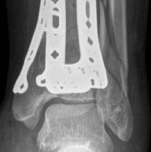

Fig 2.2-6a–b Immediate postoperative x-rays showing restoration of the ankle mortise and distal tibia alignment through anatomical and stable fracture fixation.

1. AP view.

2. Lateral view.